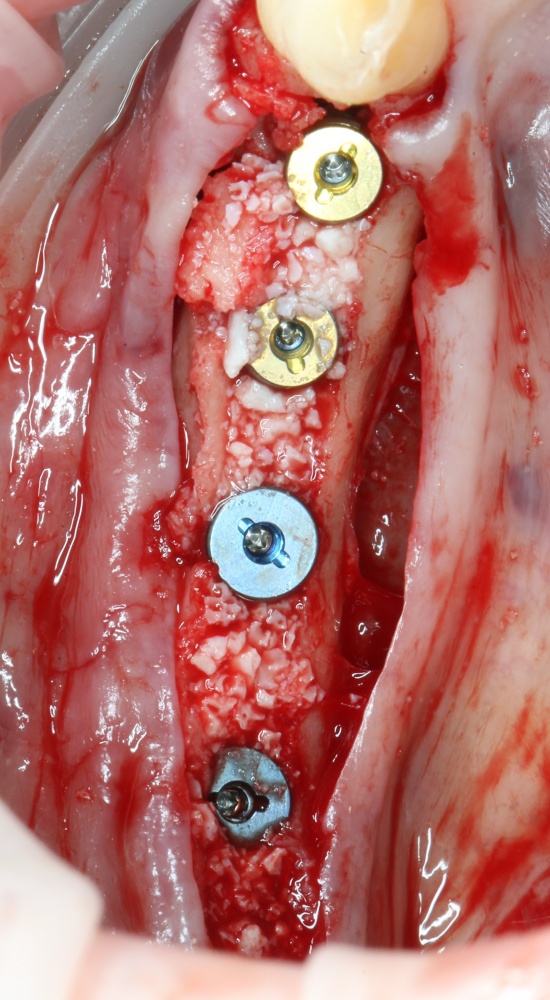

Я зафиксировал костный блок практически без адаптации на несколько винтов. Обрати внимание, что винты находятся в зоне, где не планируется установка имплантатов. Фиксация должна быть надежной, поскольку мне еще предстояла подготовка лунок для имплантатов. Трех винтов для этого вполне достаточно.

Дальнейшая адаптация костного блока свелась к сглаживанию острых краев. После чего я приступил к подготовке лунок и установке имплантатов.

Установка имплантатов.

Напомню, что для этой работы я выбрал субкрестальные имплантаты Ankylos C/X. Они прекрасно сочетаются с любым методом остеопластики.

Я не планирую установку супраструктур или коронок, поэтому на уровень первичной стабильности можно положить болт. Даже наоборот — чем меньше крутящий момент при установке, тем лучше. Для имплантатов Ankylos и подобных им, это особенно важно. В общем, момент силы при установке — не более 10-15 Нсм.

Ремарка: имплантаты с предустановленными имплантодержателями хороши тем, что с ними легко контролировать позиционирование имплантатов. В случае с Ankylos С/Х - еще и крутящий момент. Имплантодержатель должен отсоединяться от имплантата с легким щелчком. Если его клинит, и тебе приходится прикладывать для этого усилия, то ты, однозначно, превысил момент силы во время установки имплантата. Следовательно, жди проблем.

Глянем на то, что получилось:

Осталось адаптировать костный блок (убрать острые края), проверить его фиксацию и, при необходимости, добавить винты. Десятисекундное дело.